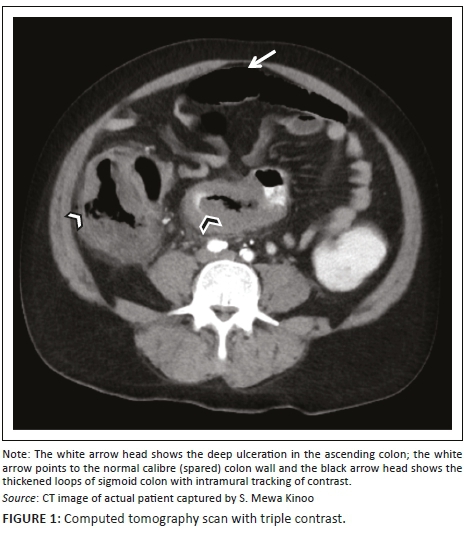

A 59-year-old male patient presented with a one-week history of progressive abdominal pain, abdominal distension and associated watery and bloody diarrhoea. There was no history of inflammatory bowel disease, nor antibiotic or herbal enema usage; the patient reported drinking only tap water. On examination, the patient, who was HIV-negative, was dehydrated, pale, pyrexial and had a tachycardia. The blood pressure was normal. The abdomen was distended with generalised tenderness but no peritonism. Rectal examination revealed blood on the glove. The patient was resuscitated and commenced on intravenous antibiotics as an infective cause for his acute abdomen was considered most likely. Plain chest radiography revealed no pneumoperitoneum, and abdominal radiography revealed a transverse colon diameter of 7 cm with neither thumb printing nor pneumatosis intestinalis. The white cell count was 34 × 109/L, haemoglobin 9 g/dL, urea 9 mmol/L and creatinine 100 µmol/L. An abdominal triple contrast-enhanced (oral, rectal, intravenous) CT scan revealed segments of grossly dilated large bowel with areas of thickening, deep ulceration, contrast tracking deep within the bowel wall and skip areas with normal bowel wall calibre (Figure 1), suggesting colitis. Colonoscopy revealed areas of inflamed and necrotic mucosa with intervening areas of normal mucosa (Figure 2). Following colonoscopy and biopsy, the patient's condition deteriorated and a post-colonoscopy perforation was suspected. At laparotomy, the entire colon was noted to be wrapped with omentum, with no signs of perforation or peritonitis (Figure 3). A diagnosis of amoebic colitis was entertained because of the omental wrapping. A diverting loop ileostomy was fashioned as the patient was haemodynamically unstable. Anti-parasitic treatment was commenced immediately post-operatively; however, despite this, the patient deteriorated and demised. Histopathological evaluation of the colonoscopically guided biopsy confirmed the diagnosis of amoebic colitis (Figure 4).

In a case report, Ying et al. report extended submucosal ulcers with intramural dissection of contrast as the characteristic CT scan finding of FAC.8 This feature (noted in our patient) represents the underlying flask-shaped ulcer pathology typical of amoebiasis and excludes other infective, inflammatory or ischaemic bowel diseases (Figure 1). Other non-specific findings (not noted in our patient) include the target sign indicating pancolitis and discontinuous bowel necrosis depicted by alternating enhancing and non-enhancing bowel wall. The latter confirms the vascular occlusion associated with FAC.9